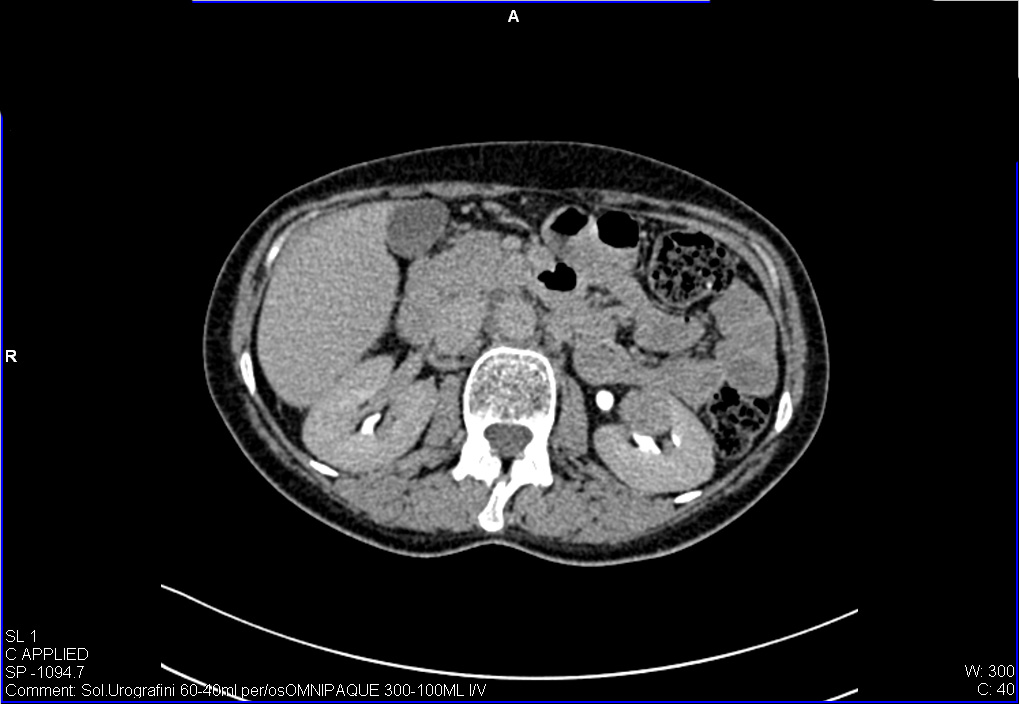

Женщина средних лет, жалоб нет.

УЗИ почек - малый рак. Small RCC.

Позвонили пациентке, она сделала КТ - новообразование подтверждено.